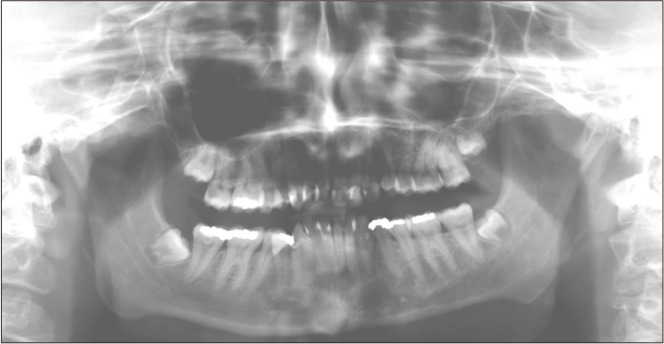

Neurofibromatosis type 1 (NF1) is an autosomally dominant tumor suppressor syndrome and multisystem disease. Central giant-cell granulomas (CGCGs) can be seen in patients with NF1. A 21-year-old female was diagnosed with two CGCGs, one in the mandible and then one in the maxilla, in a 7-year period. Increased incidence of CGCGs in NF1 patients was thought to be caused by an underlying susceptibility to developing CGCG-like lesions in qualitatively abnormal bone, such as fibrous dysplasia. However, germline and somatic truncating second-hit mutations in the NF1 gene have been detected in NF1 patients with CGCGs, validating that they are NF1-associated lesions. Oral manifestations in patients with NF1 are very common. Knowledge of these manifestations and the genetic link between NF1 and CGCGs will enhance early detection and enable optimal patient care.